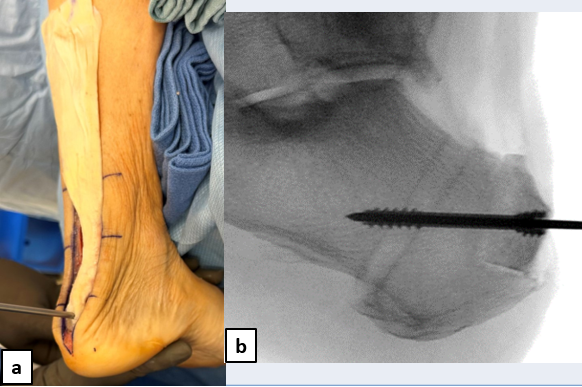

A healthy 66-year-old female who presented at our office via urgent care referral for a chronic left Achilles tendon rupture. She had been diagnosed by an another provider with Achilles tendinitis with retrocalcaneal spurring (Figure 1a) several months prior and had been working with physical therapy. She presented to urgent care with concern for possible deep vein thrombosis (DVT) as she experienced worsening calf pain while trying to walk for the previous couple of weeks. She had no recollection of a provoking injury, so the exact timing of rupture is unknown, but it likely took place about 7 weeks prior. Urgent care obtained updated radiographs and a magnetic resonance imaging (MRI) study (Figures 1b & 2).

Following administration of general anesthesia, we placed a thigh tourniquet on the patient in prone position. A full-thickness longitudinal midline linear incision over the palpable dell extended distally over the posterior aspect of the calcaneus. We carried blunt dissection deeper to visualize the full-thickness tear (Figure 3). Next, we harvested the flexor hallucis longus (FHL) tendon using the short harvest technique (Figure 4). Subsequently, we remodeled the posterior aspect of the calcaneus to remove any underlying pathology.